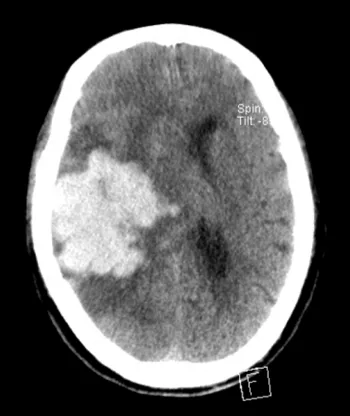

經(jīng)頭顱CT檢查

明確是極為嚴重的腦出血

出血量竟高達95ml